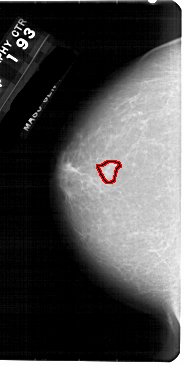

FILE: A_1948_1.LEFT_CC.OVERLAY

TOTAL_ABNORMALITIES 1

ABNORMALITY 1

LESION_TYPE MASS SHAPE IRREGULAR MARGINS ILL_DEFINED

ASSESSMENT 4

SUBTLETY 3

PATHOLOGY BENIGN

TOTAL_OUTLINES 1

BOUNDARY